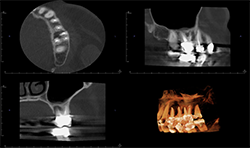

Two-dimensional imaging can’t evaluate the volume of the alveolar process accurately, especially in the buccolingual direction (Fig. 3)

CBCT imaging shows the volume of the alveolar process in any direction for implant treatment planning. (Figs. 4A, 4B) CBCT software allows one to measure the height and width of the alveolar ridge (Fig. 4C). This patient doesn’t have adequate bone volume for implant placement in the posterior left maxilla (Fig. 4D). Due to the severe alveolar ridge resorption, gaining adequate bone volume was recommended.

Fig. 3

Fig. 4A

Fig. 4B

Fig. 4C

Fig. 4D